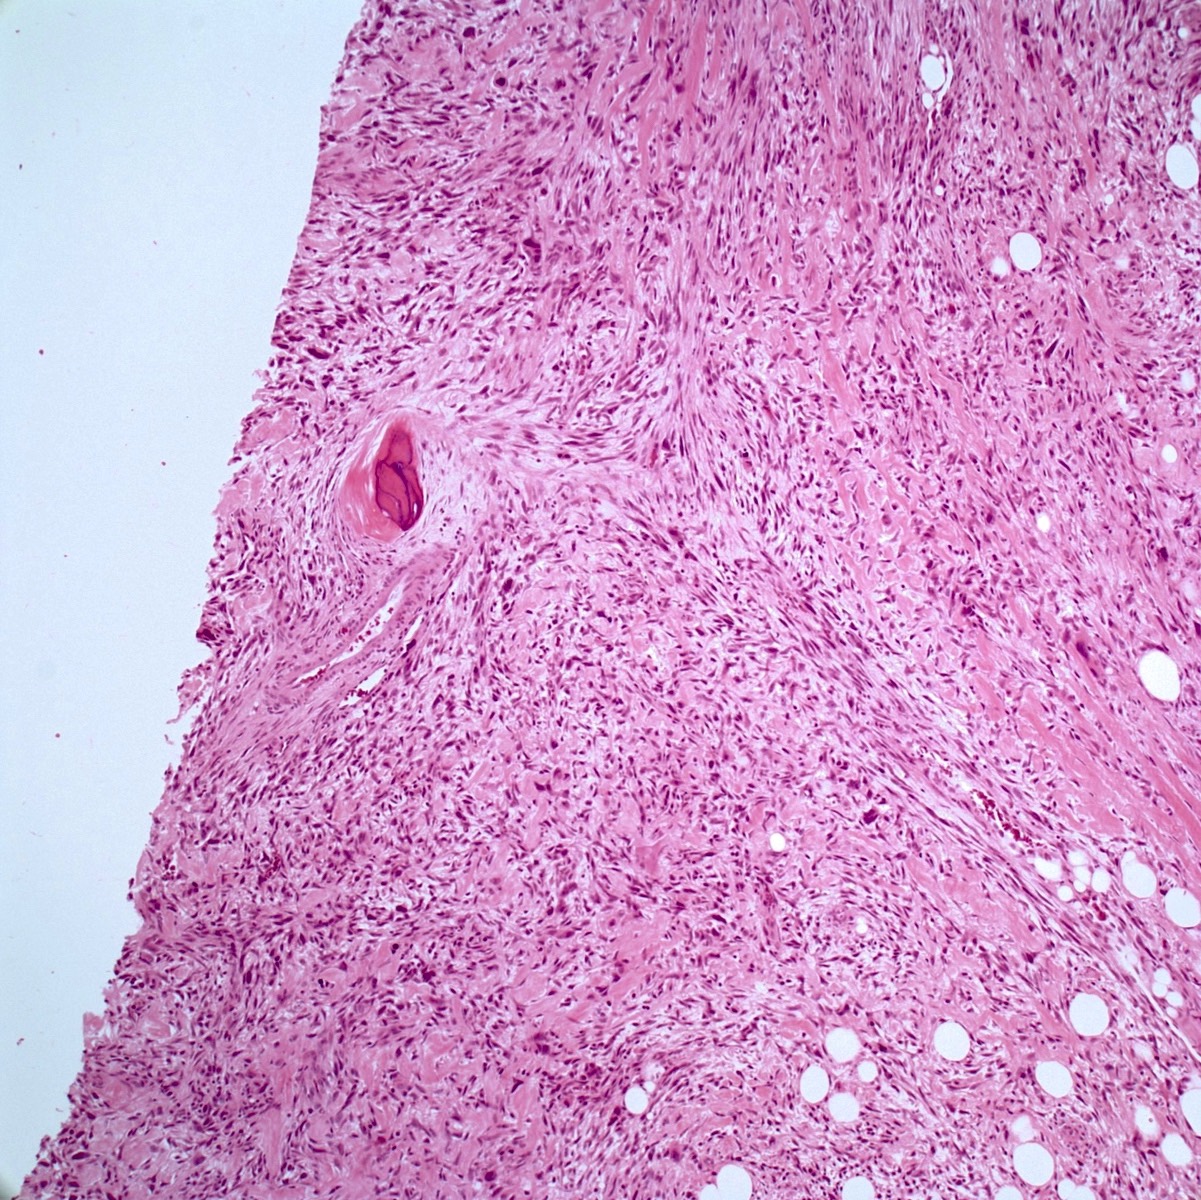

- Low grade central osteosarcoma:

- Permeative growth:

- Intramedullary (surrounds and erodes native trabeculae, fills Haversian systems)

- Cortical destruction and soft tissue invasion

- Neoplastic cells: fibroblast-like spindle cells (minimal atypia); hypocellular to moderately cellular

- Scattered mitoses may be seen

- Rare, scattered higher grade areas may be present

- Arranged in fascicles or interlacing bundles

- Neoplastic bone:

- Bone trabeculae (fibrous dysplasia-like): curved, branching or interanastomosing

- Longitudinal lamellar bone: like parosteal osteosarcoma

- Benign multinucleated giant cells: present in 33% of cases

- With or without scattered foci of atypical cartilage

- Dedifferentiation / high grade transformation (10 - 35% of cases):

- High grade osteosarcoma

- High grade undifferentiated pleomorphic sarcoma

- Fibrosarcoma

- Most common in recurrent tumors (2 - 3 years after resection) but may be seen in the primary tumor

- Permeative growth:

Microscopic (histologic) images

Contributed by Jesse Hart, D.O., Borislav A. Alexiev, M.D. and AFIP

A 12 year old girl has a 10.5 cm intramedullary mass in the distal femur, which was resected (see gross and microscopic images). High power views demonstrate bland spindle cells. Which of the following is most accurate regarding this tumor?

- Most likely, genetic abnormality is amplification of the MDM2 gene

- Most likely, genetic abnormality is a mutation in TP53

- Patient likely has lung metastases

- Tumor likely has a GNAS mutation

- Unusual tumor in the pediatric population

Practice answer #1

A. Most likely, genetic abnormality is amplification of the MDM2 gene. The tumor is a low grade central osteosarcoma.